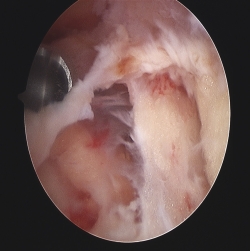

Siguiendo por los recesos lateral y medial (Figura 5) se llega a la zona suprapatelar, cuya fibrosis es la primera causa de limitación de la flexión (Figura 6). En este espacio hay que ser muy meticuloso para resecar con motor (Figura 7) y radiofrecuencia las adherencias, los nódulos, cíclopes (Figura 8), la fascia profunda del cuádriceps, con esqueletización de la cara anterior de fémur si es necesario, y liberar el alerón externo e interno, en función de la rótula: si está lateralizada (liberación solo lateral) o bien centrada (liberación lateral y medial), para facilitar el recorrido rotuliano. La limpieza de este espacio es fundamental para recuperar el máximo grado de flexión.

Figura 8. Nódulo fibroso entre polo superior de rótula y tendón cuadricipital. Resalte y dolor en prótesis con estabilización posterior.